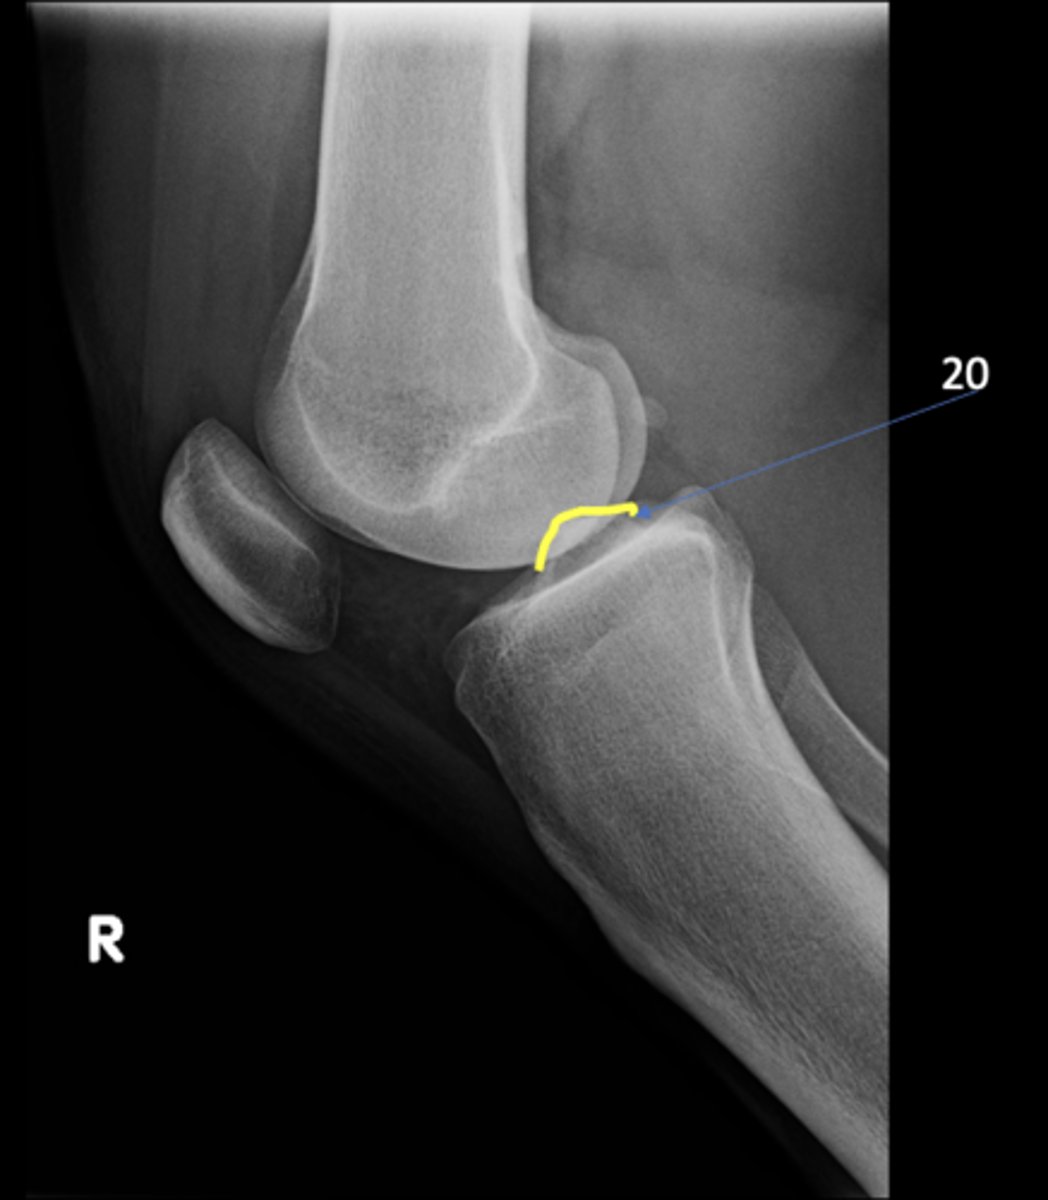

ID 9

<p>ID 9</p>

10

Intercondylar eminence

ID 20

<p>ID 20</p>